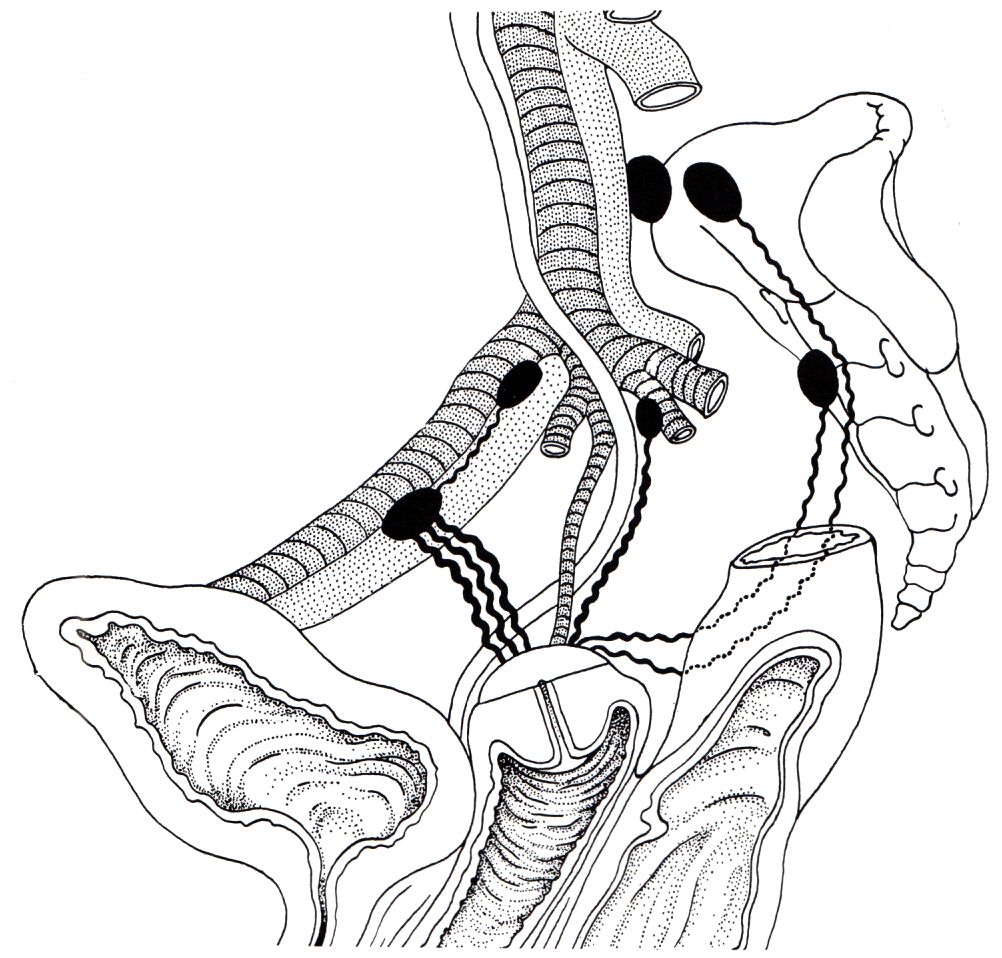

Lymphabfluss

Metastasierung